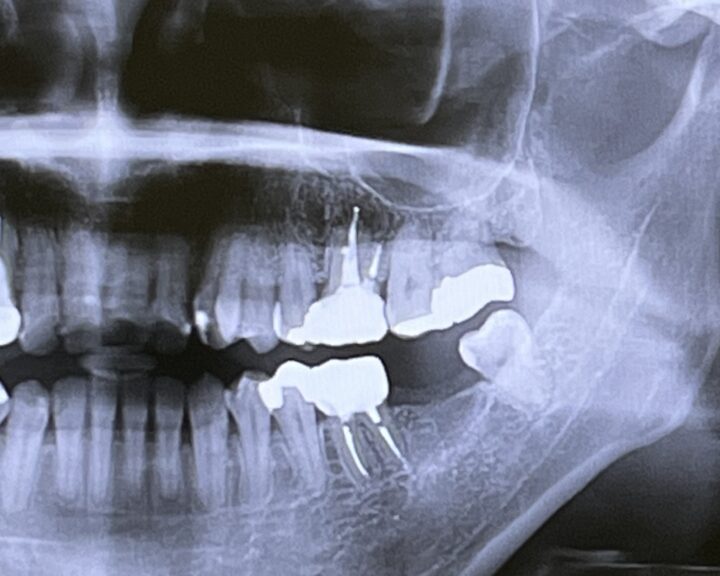

インプラント治療では、事前にお口の中を「見える範囲」だけで判断せず、骨や周囲の状態を含めて丁寧に確認することが大切です。そのために行うのが、歯科用CTやレントゲンによる精密検査です。

とくにインプラントは、顎の骨の中へ人工の歯根を埋め込む治療方法のため、「どの位置に、どの角度で、どの深さで」進めるかを考える必要があります。歯科用CTは、こうした検討に役立つ検査の一つです。

当院では、検査結果をもとに、歯周病の有無や進み具合、日常の磨き残しが出やすい部分なども併せて確認します。歯周病が進行している場合は、インプラントの検討と並行して、お口の環境づくりから始めることがあります。